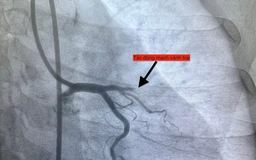

Nhồi máu cơ tim: Nhận biết, dự phòng và điều trị hiệu quả

Nếu không được phát hiện sớm và kiểm soát kịp thời, các yếu tố nguy cơ như: tăng huyết áp, rối loạn mỡ máu, xơ vữa động mạch… có thể dẫn đến biến cố nghiêm trọng như nhồi máu cơ tim.